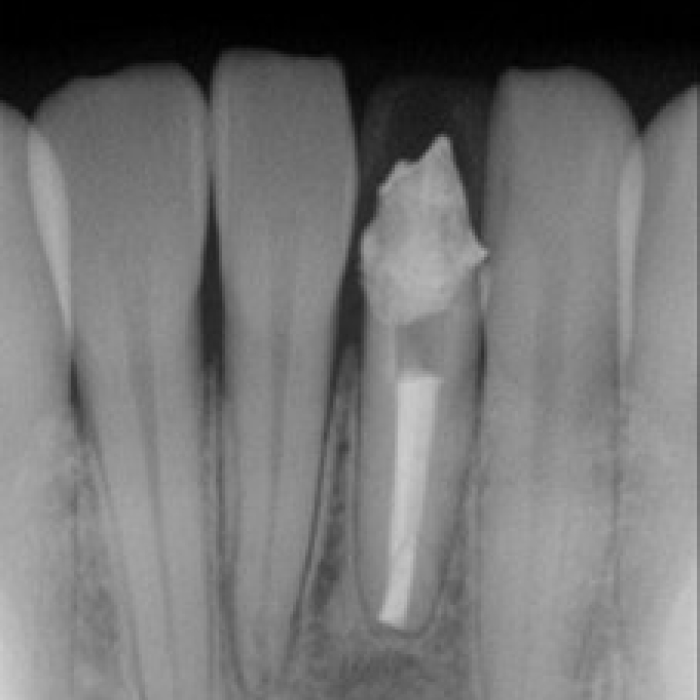

신경치료 전후 사례

• 치료전

치료후